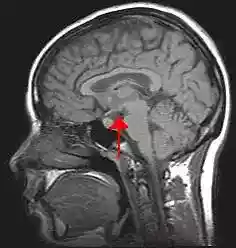

Location of the human hypothalamus | |

Location of the hypothalamus (blue) in relation to the pituitary and to the rest of the brain | |

The hypothalamus (from Ancient Greek ὑπό, "under", and θάλαμος, "chamber") is a portion of the brain that contains a number of small nuclei with a variety of functions. One of the most important functions of the hypothalamus is to link the nervous system to the endocrine system via the pituitary gland. The hypothalamus is located below the thalamus and is part of the limbic system.[1] In the terminology of neuroanatomy, it forms the ventral part of the diencephalon. All vertebrate brains contain a hypothalamus. In humans, it is the size of an almond.

Human hypothalamus (shown in red)